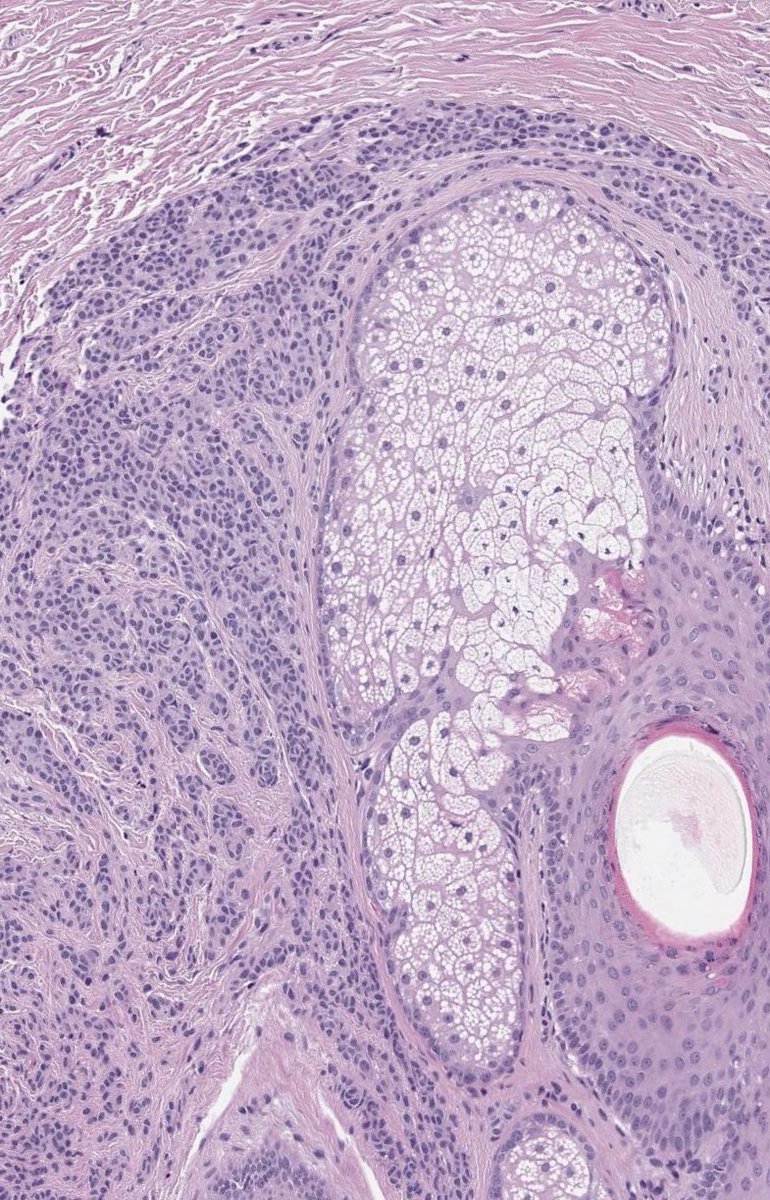

Highly revealing adnexal invasion of melanoma. Special thanks to my friend and colleague, Dr. Marina Muratova Marina Muratova , for the case. #dermpath #dermtwitter #PathTwitter

Highly revealing adnexal invasion of melanoma.

Special thanks to my friend and colleague, Dr. Marina Muratova <a href="/MuratovaMV/">Marina Muratova</a> , for the case.

#dermpath #dermtwitter #PathTwitter